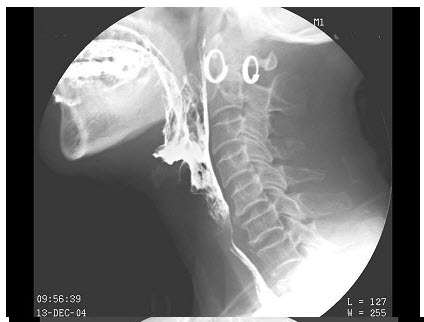

- 单项选择题女,73岁,吞咽困难2月。体检:咽充血,滤泡增生,最可能的诊断为()

- C